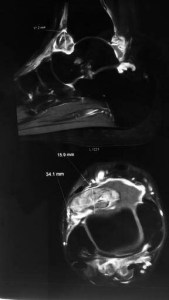

An MRI scan of his right ankle was done and it showed an intra-articular nodule / tumour over the front of his right ankle. It was consistent with a pigmented villonodular synovitis (PVNS).

This tumour has been growing in his right ankle for a long time. It was dormant and asymptomatic until one fine day when he caught part of the tumour between the surfaces of the joint. This caused bleeding and occasional “infarction” of the tumour. This leads to the acute onset of pain and swelling as in this case.